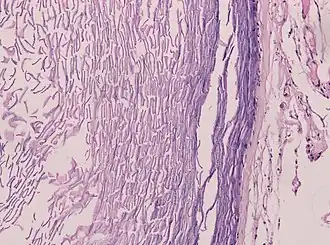

Histopathology, showing a keratinizing stratified squamous epithelium, and a lumen containing keratin flakes -

Histopathology showing epithelium and lamellated keratin (left)